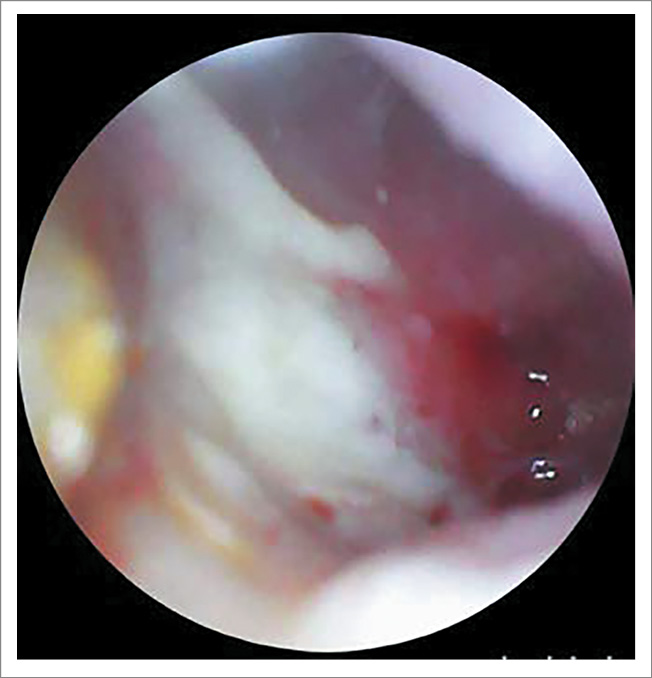

Ежедневно во время нахождения пациентки в стационаре проводился туалет ушей под микроскопом с использованием 0,5% раствора Диоксидина и дексаметазона. На фоне проводимого лечения на 7-е сутки жалобы и отоскопическая картина оставались прежними, в связи с чем принято решение о проведении хирургического вмешательства на правом ухе в объеме антромастоидотомии с ревизией барабанной полости (рис. 6, 7).

Рис. 6. Отоскопическая картина справа после курса консервативной терапии: тотальная перфорация БП, слизистая медиальной стенки барабанной полости утолщена, покрыта серо-белым субстратом (фибрин? некротические ткани?).

Рис. 7. Отоскопическая картина слева после курса консервативной терапии: БП утолщена, местами гиперемирована, в передних отделах визуализируется центральная перфорация диаметром 2 мм.